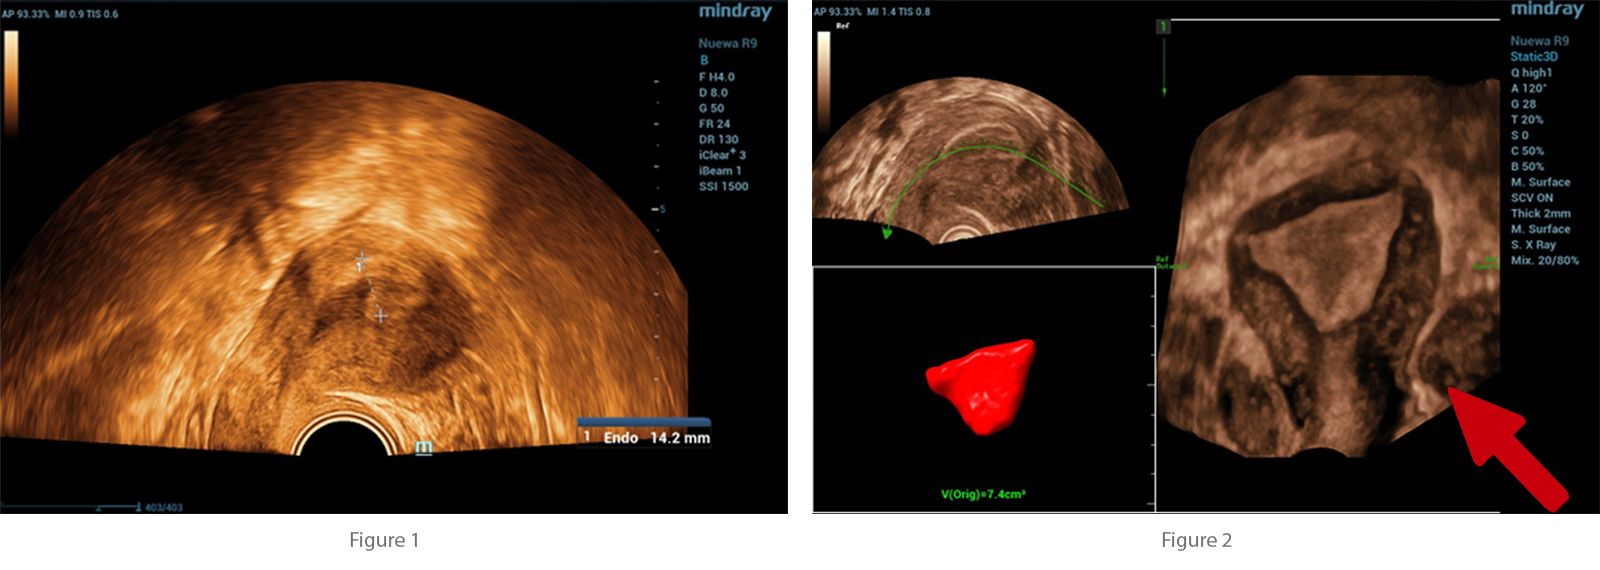

Initial investigations included a urine pregnancy test, which returned positive. Transvaginal ultrasound was performed, revealing an anteverted, non-gravid uterus with no abnormal myometrial shadowing. The endometrium measured 14.2 mm.?

All ultrasound examinations were performed using the Nuewa R9 Ultrasound System (Mindray, Shenzhen, China). A convex transducer (SC6-1U) was employed for general pelvic evaluation, and a 4D transvaginal transducer (DE11-3WU) was used for detailed assessment of the uterus and adnexa. Imaging modalities included two-dimensional (2D) grayscale ultrasound, Color Doppler, and four-dimensional (4D) imaging.

To enhance diagnostic accuracy, advanced imaging applications were applied. Smart Endometrial Receptivity Analysis (Smart ERA) was utilized to assess endometrial morphology and volume, while the SCV+ function was employed to improve spatial resolution and delineation of adnexal structures. These features contributed to the precise characterization of the ectopic gestational sac and detailed evaluation of ovarian and endometrial parameters.